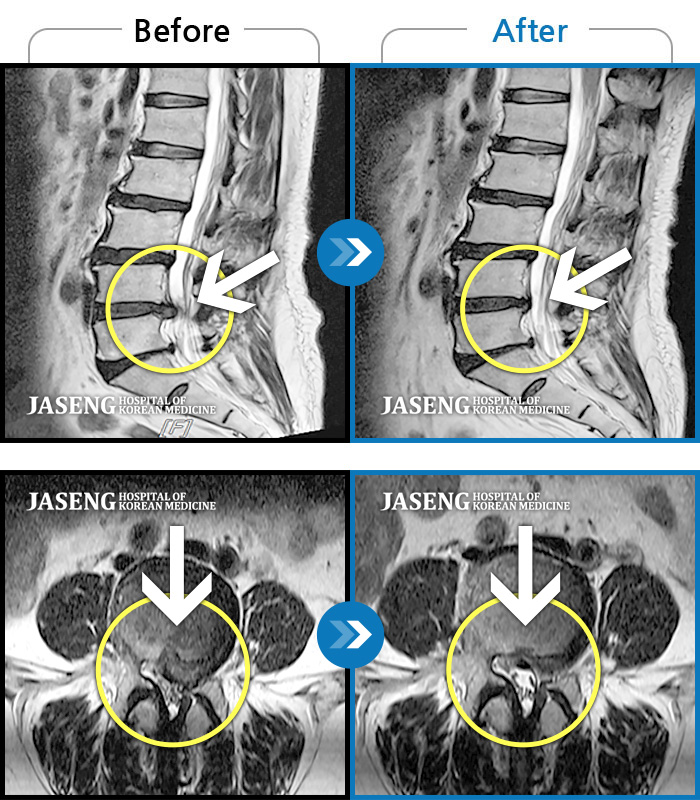

Before

After

환자에게 사전 동의를 받아 동일 조건에서 촬영되었습니다.

개인에 따라 치료 후 부작용이 발생할 수 있으니 의료진과 상담 후 치료를 진행하시기 바랍니다.

좌하지 방사통, 야간통

엉치 통증 및 우측 종아리 후면 통증